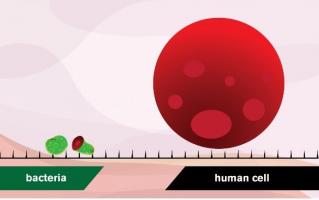

INFECTIONS NOSOCOMIALES et ANTIBIORÉSISTANCE : Quand les bactéries se partagent des gènes mortels

Actualité publiée le 11/06/2022ANTIBIOFOULING : Prévenir les IAS mais sans antibiotiques

Actualité publiée le 29/10/2023INFECTION URINAIRE : Savoir l'éviter avec le cathéter